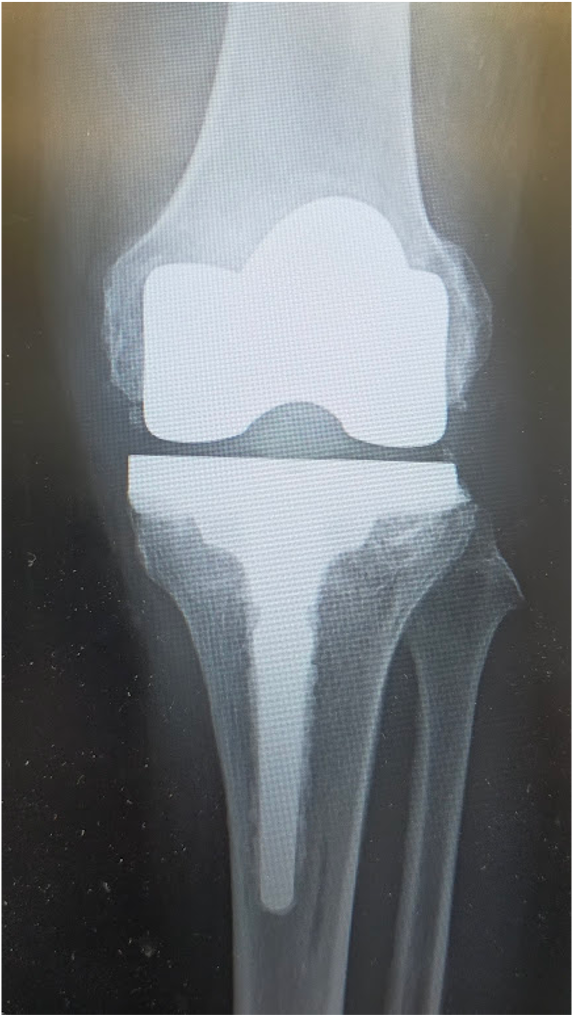

関節のなかで傷んだ部分だけ(多くは内側の半分だけ)を人工関節に置換します。メリットは手術の傷や削る骨の量が少ないため、術後の痛みも少なく、回復が早く、膝の曲がりもよいところです。耐久性も悪くありませんが、人工膝関節全置換術と比べると若干手技が難しく、適応をしっかり選ぶ必要があります。変形が比較的軽く、外側の軟骨や靭帯に異常がないなど、術前に専門医の診断を受けた上で、相談するようにしましょう。

UKAの術後

当院にて右人工膝関節全置換術(TKA)を施行。術前、歩行も困難でしたが、術後は杖歩行も安定し、良好な可動域も獲得。入院中に反対側の人工膝関節単顆置換術(UKA)も行い、十分なリハビリ後に退院となりました。

〈手術前〉

〈手術後〉(右ひざ)

〈手術後のレントゲン〉

左TKA後

〈手術後のレントゲン〉(正面・側面)

左膝